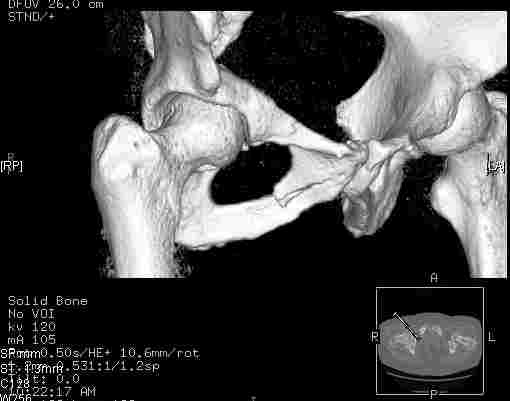

Удалось сегодня вывести пациентку в соседнюю больницу, где есть кт. Срезы сделаны только горизонтальные.

Следом 3d